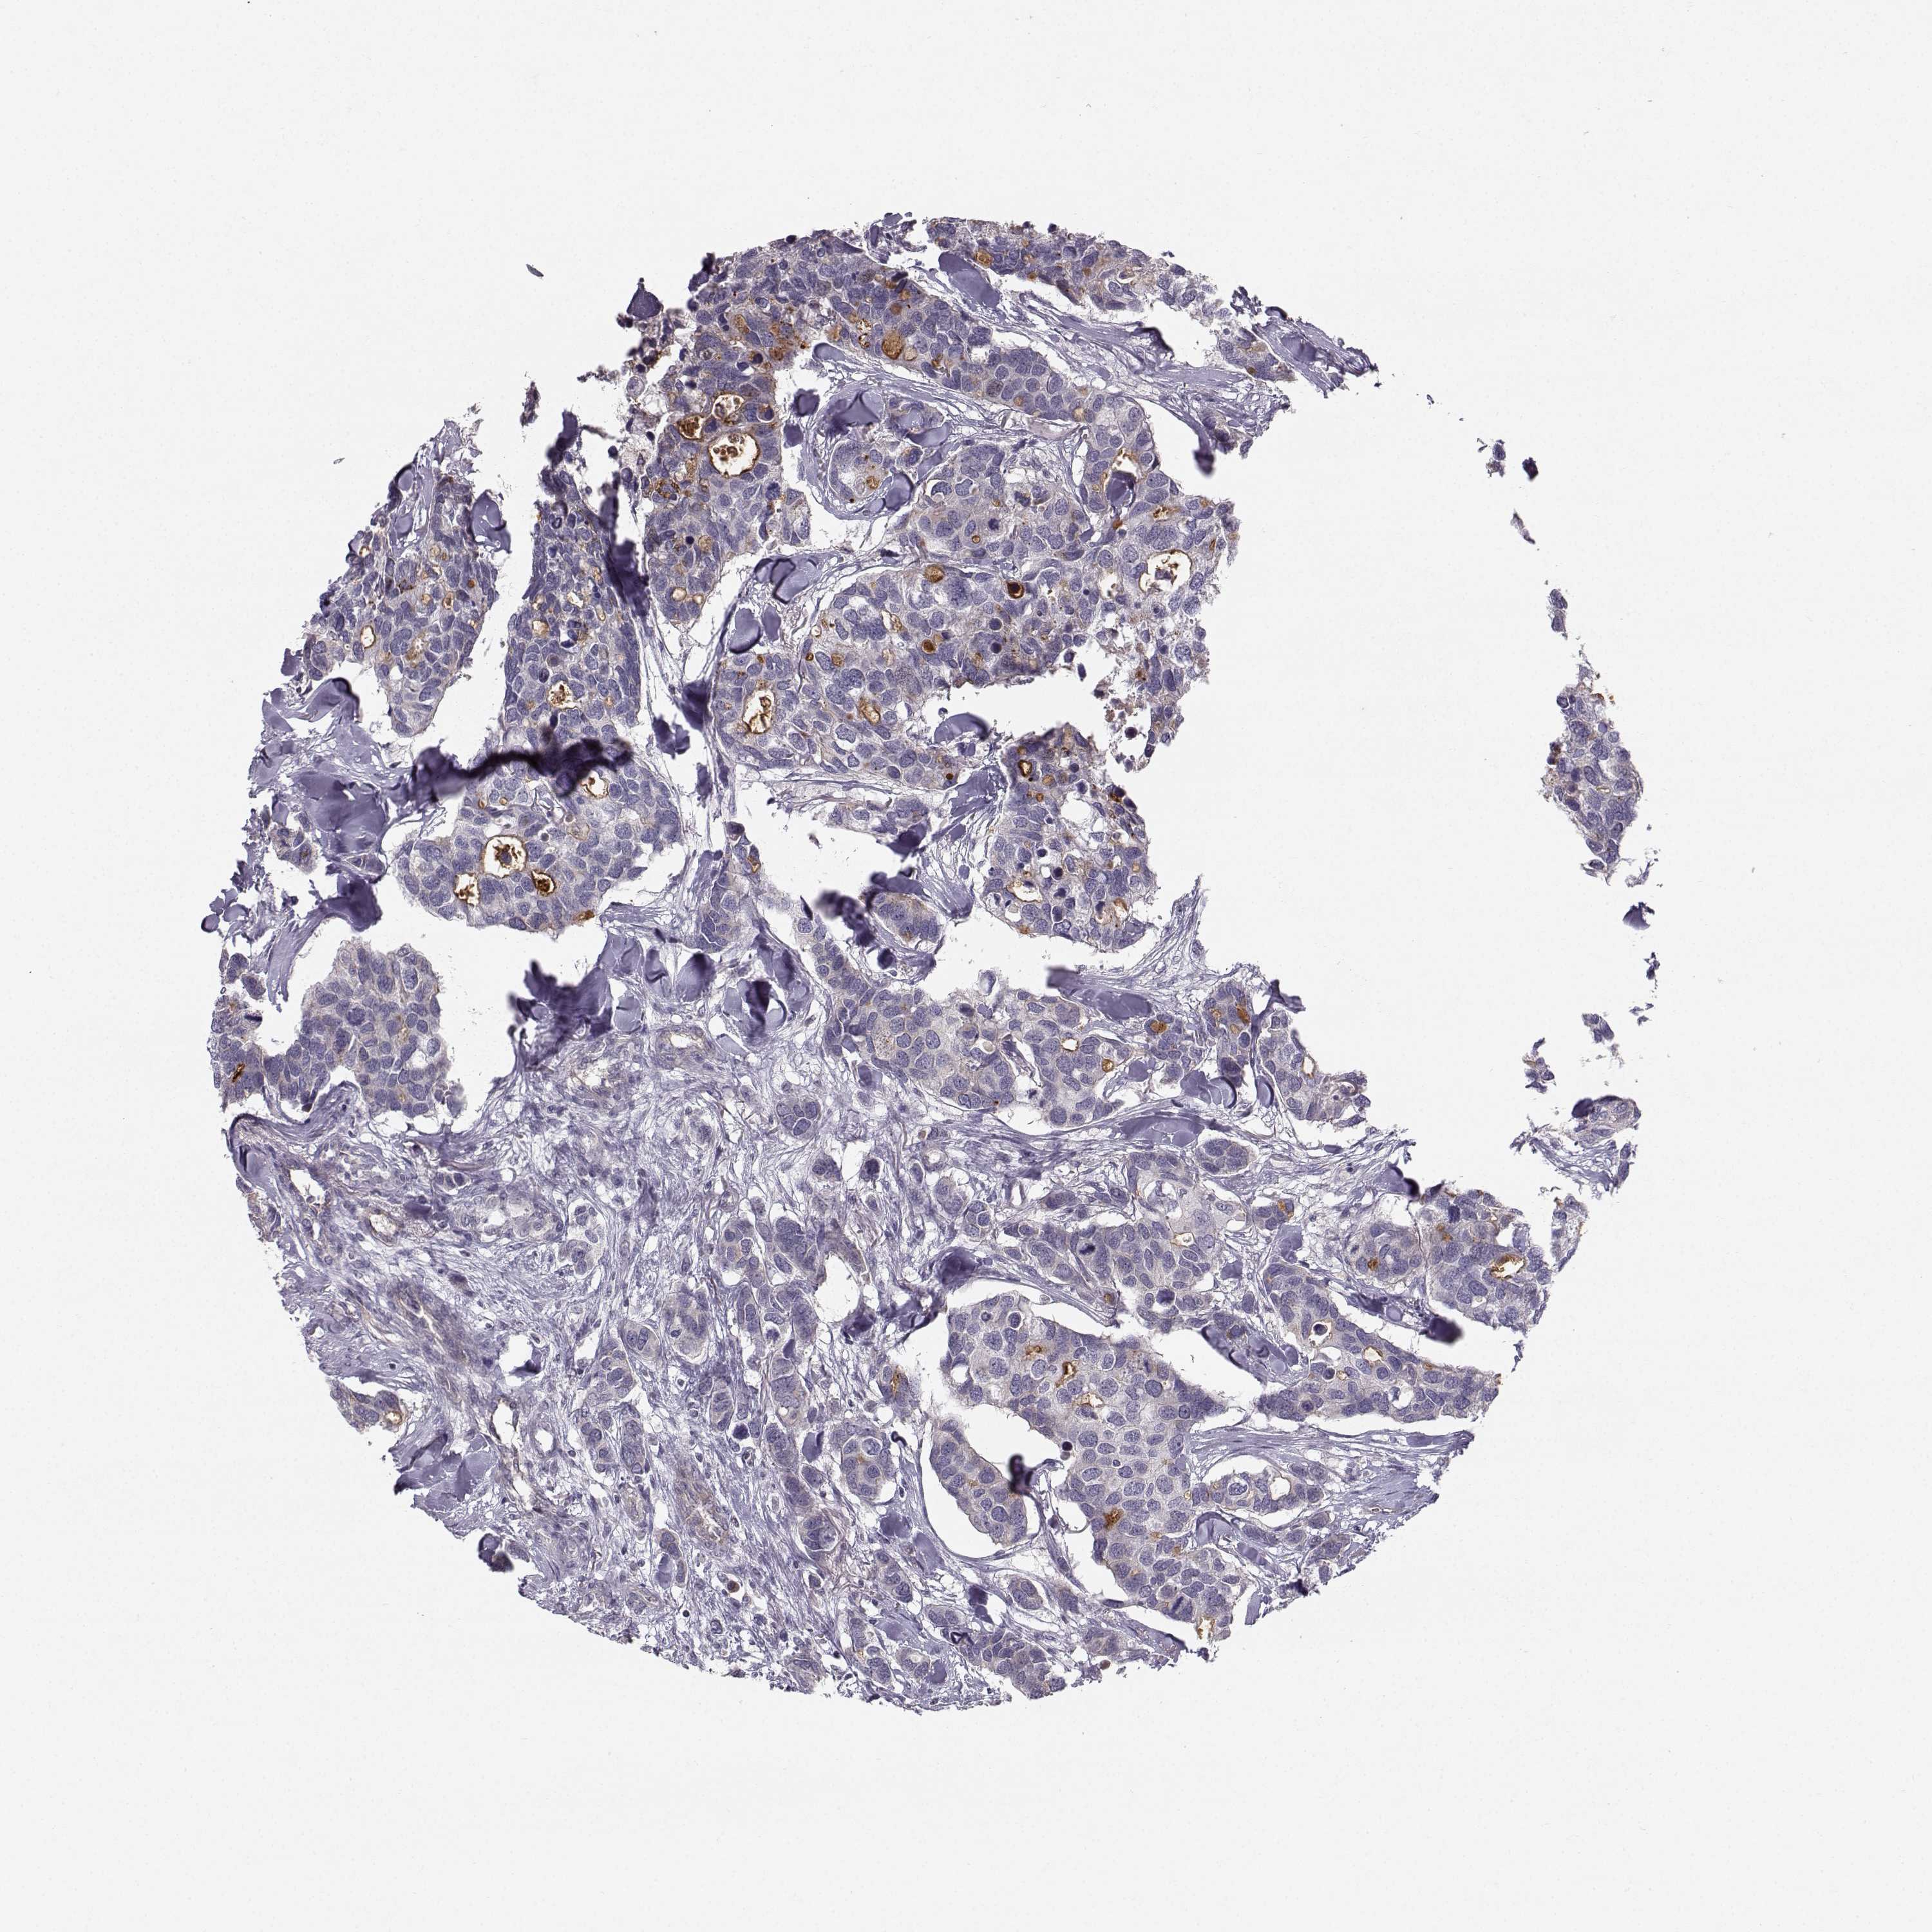

BRCA TCGA BRCA VALIDATION PROTEIN EXPRESSION

Breast cancer

Human cancer